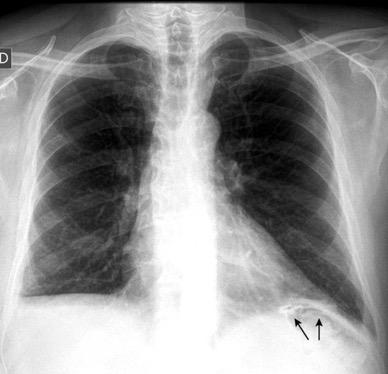

Derrame pleural 43-48% de pacientes con embolismo.

< 1/3 de hemitórax: 90%.(puede haber en lado opuesto).

Siempre exudados.

75% de los pacientes con TEP y derrame pleural tienen dolor pleurítico.

La disnea desproporcionada

Joroba de Hampton

Hallazgo muchas veces incidental.